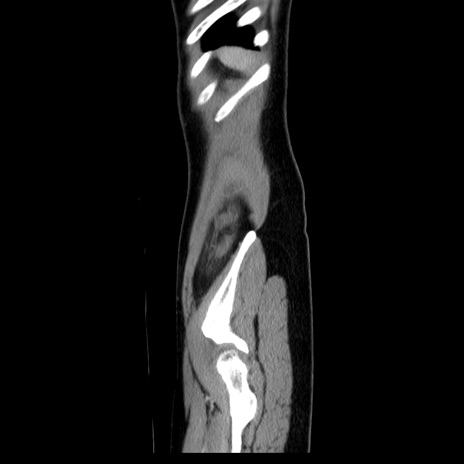

症例39(矢状断像)

【症例】40歳代女性

【主訴】上下腹部痛

【現病歴】2日目から下腹部痛あり。夜間は痛みで眠れなかった。昨日より上腹部痛と下痢が出現。臥位で痛みは軽快したため、休んでいた。本日になって臥位でも立位でも痛みが強くなってきたため救急要請。

【既往歴】子宮内膜症

【身体所見】部:平坦・軟、左上下腹部に圧痛あり、反跳痛あり。

【データ】WBC 21800、CRP 26.78

CT